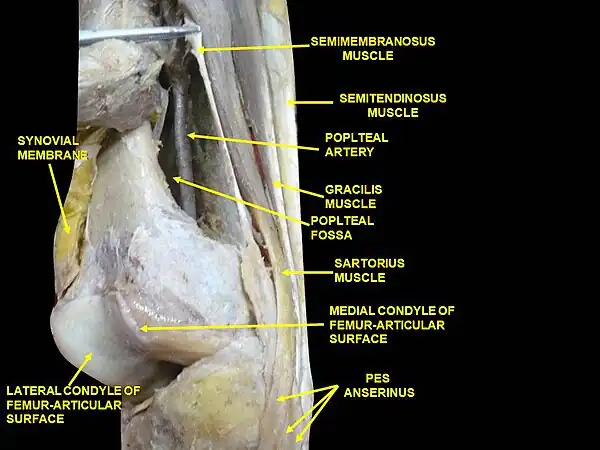

The lower extremity of the femur (or distal extremity) is the thickest femoral extremity, the upper extremity is the shortest femoral extremity. It is somewhat cuboid in form, but its transverse diameter is greater than its antero-posterior (front to back). It consists of two oblong eminences known as the condyles.[3]

Anteriorly, the condyles are slightly prominent and are separated by a smooth shallow articular depression called the patellar surface. Posteriorly, they project considerably and a deep notch, the Intercondylar fossa of femur, is present between them. The lateral condyle is the more prominent and is the broader both in its antero-posterior and transverse diameters. The medial condyle is the longer and, when the femur is held with its body perpendicular, projects to a lower level. When, however, the femur is in its natural oblique position the lower surfaces of the two condyles lie practically in the same horizontal plane. The condyles are not quite parallel with one another; the long axis of the lateral is almost directly antero-posterior, but that of the medial runs backward and medialward. Their opposed surfaces are small, rough, and concave, and form the walls of the intercondyloid fossa. This fossa is limited above by a ridge, the intercondyloid line, and below by the central part of the posterior margin of the patellar surface. The posterior cruciate ligament of the knee joint is attached to the lower and front part of the medial wall of the fossa and the anterior cruciate ligament to an impression on the upper and back part of its lateral wall.[3]

The articular surface of the lower end of the femur occupies the anterior, inferior, and posterior surfaces of the condyles. Its front part is named the patellar surface and articulates with the patella; it presents a median groove which extends downward to the intercondyloid fossa and two convexities, the lateral of which is broader, more prominent, and extends farther upward than the medial.[3]

Each condyle is surmounted by an elevation, the epicondyle. The medial epicondyle is a large convex eminence to which the tibial collateral ligament of the knee-joint is attached. At its upper part is the adductor tubercle and behind it is a rough impression which gives origin to the medial head of the gastrocnemius. The lateral epicondyle which is smaller and less prominent than the medial, gives attachment to the fibular collateral ligament of the knee-joint.[3]